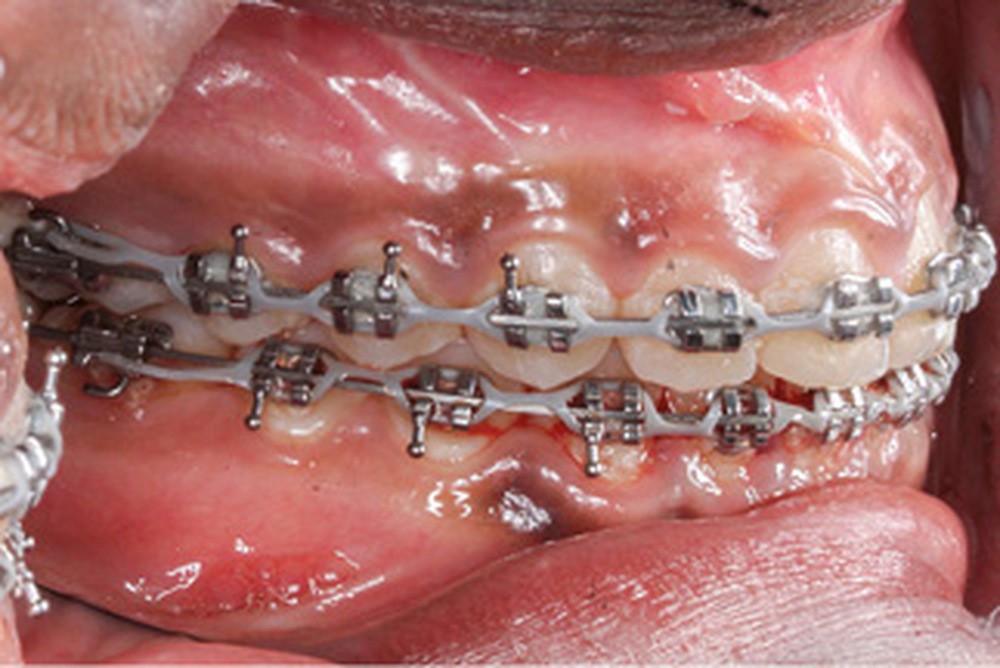

Phase thérapeutique

Un protocole ortho-chirurgical en chirurgie première a été retenu. Les étapes de traitement ont été les suivantes : motivation à l’hygiène bucco-dentaire et rééducation des fonctions, puis pose de l’appareil multi-attache edgewise conventionnel avec des arcs aciers .016x.022 passifs adaptés aux deux formes d’arcades, et enfin avancée de 6 mm et génioplastie d’avancée sur ces mêmes arcs.

Lors de la réévaluation post-chirurgicale, l’examen exo-buccal montre peu de changement, excepté l’occlusion et l’harmonie labiales retrouvées. Le surplomb et le recouvrement sont normalisés et le brossage amélioré. Les formes d’arcade sont concordantes, les médianes inter-incisives recentrées et les molaires et canines en classe I.